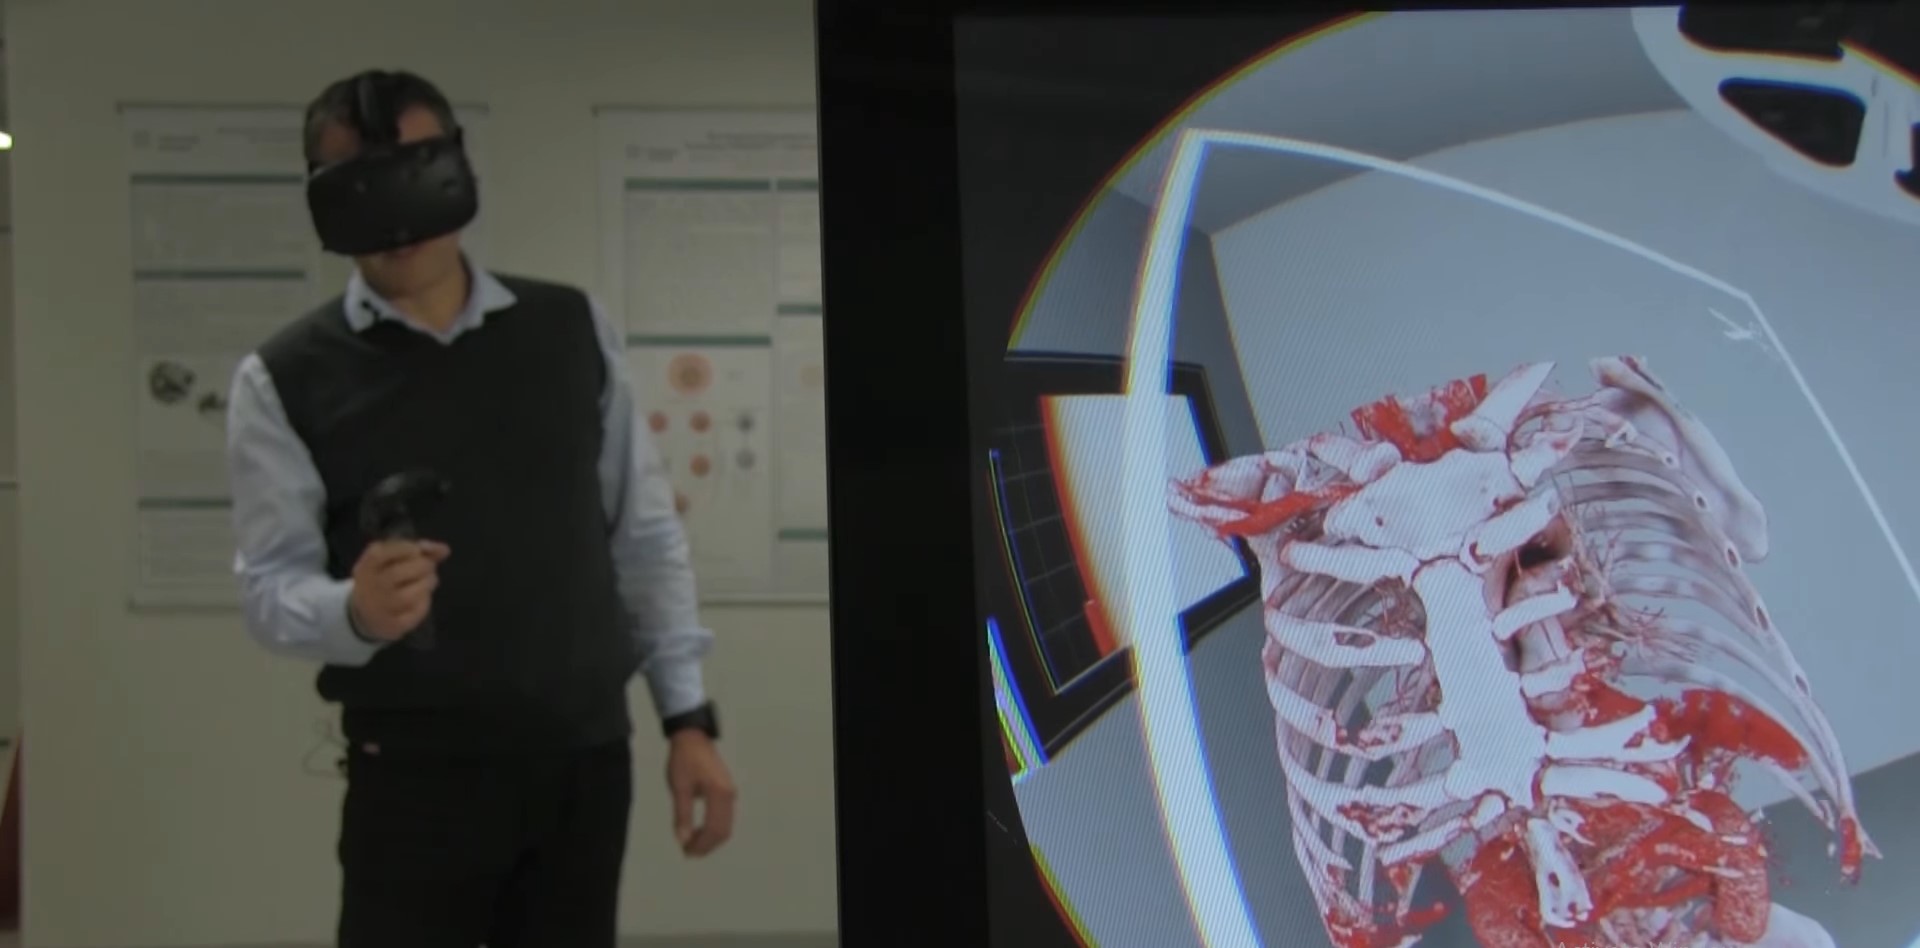

Virtual reality has been used to create an immersive and interactive environment. Virtual Reality (VR) can be full, semi, or non immersive [2]. Full immersive VR (ex. Oculus Rift and HTC Vive, illustrated in Figure 1) displays a virtual image while the real surroundings are excluded from view [3].

Different visualization and interaction techniques have been developed: The University of Basel has developed the "SpectoVive" VR medical visualizations project, illustrated in Figure 2, which uses a hardware controller and places the user in a dedicated virtual room [5], while in the US, the "DICOM VR" [77] has been developed; however both projects have some limitations such as the hardware controller and full immersion (can not be used during live interventions for reasons of hygiene and surroundings awareness).